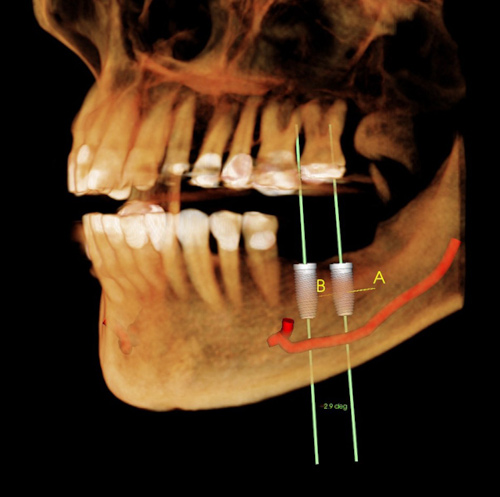

Endommagement du nerf dentaire inférieur (NDI)

Le nerf dentaire parcourt la mâchoire inférieure. Lors de la pose d'un implant traditionnel, il y a un risque d'endommagement de ce nerf lors du forage dont le diamètre est important. Les résultantes peuvent être très gênantes pour le patient. Paralysie ou perte de sensibilité d'un côté du visage, des lèvres et des dents. Parfois, le nerf peut simplement avoir été touché sans avoir subi de lésions. Dans ce cas, la perte de sensibilité est passagère.